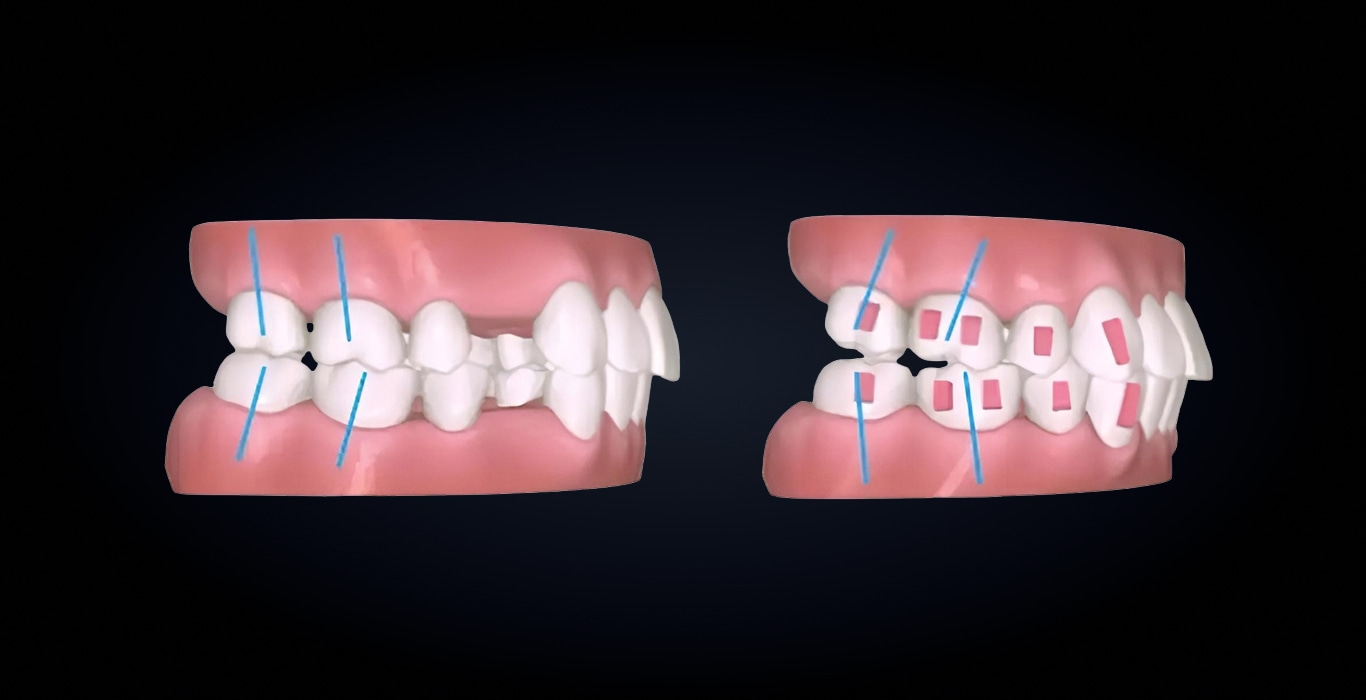

Повышает предсказуемость ортодонтического лечения с удалением первых премоляров. Обеспечивает точный контроль перемещений зубов за счет грамотного расположения аттачментов, прогнозируемых протоколов перемещений зубов с заложенными гиперкоррекциями по ангуляциям и торкам.

Протокол основан на алгоритмах платформы masterForce⁴ и многолетнем опыте работы с сотнями тысяч кейсов.